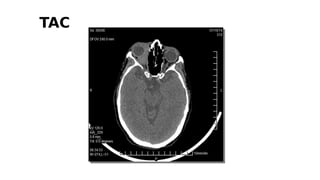

TAC

REPORTE TOMOGRÁFICO

Se encontró una masa intraconal en órbita derecha con

desplazamiento axial del globo ocular, con densidad similar a la de

los músculos extraoculares, captación de medio de contraste y

enmascaramiento parcial del nervio óptico. No se demostró

compromiso óseo ni intraocular aparente.